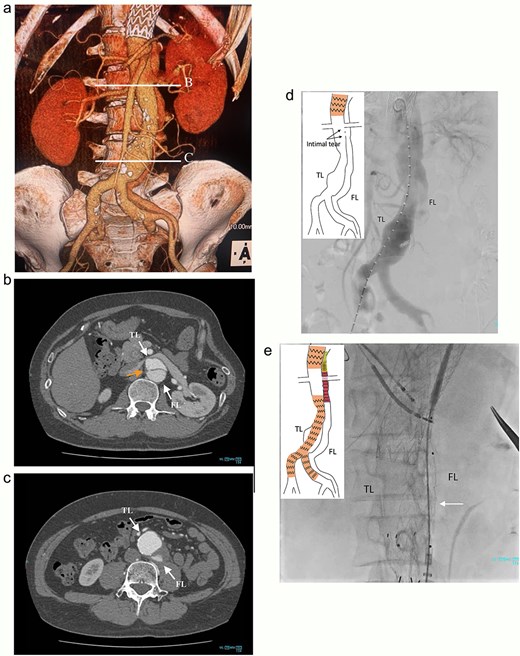

At 2-year post-procedure, CT follow-up showed AAA expansion to 56 mm, and FL dilation to 25 mm. The contrasted CT showed small inflow to the FL from the TL through the gap between the intimal flap and the FL stent graft via a residual intimal tear, as well as reversal flow from re-entry at the EIA (Fig. 2a–c). A second-stage endovascular repair was planned for completing the TAAA repair. Under local anesthesia, the gap between the FL stent graft and the intimal flap was occluded using DELTAFIL (Jonson & Jonson, NJ, USA) from FL side to close a residual intimal tear (Fig. 2d). The eighth intercostal artery and the third lumbar artery were occluded using DELTAFIL and GARAXY G3 (Jonson & Jonson, NJ, USA), respectively to block the backflow from these side branches. Then the 8 × 59 mm VBX (WL Gore & Associates, Newark, DE, USA) was deployed at left EIA covering the re-entry tear, successfully completing FL closure (Fig. 2e). The postoperative course was uneventful, with no paraplegia, and he was discharged on the postoperative day 4. The postoperative contrast-enhanced CT showed no contrast inflow into the FL. The CT imaging 3 years after the procedure showed the reduced diameter of abdominal aorta of 35 mm (Fig. 3a–c).

The postoperative contrast-enhanced CT axial images 3 years after the procedure showed no contrast inflow into the FL, and the reduced diameter of post-dissection thoracoabdominal aortic aneurysm at thoracic level (a), renal artery level with FL stent graft (b; white arrow), and abdominal level (c). TL: true lumen; FL: false lumen.